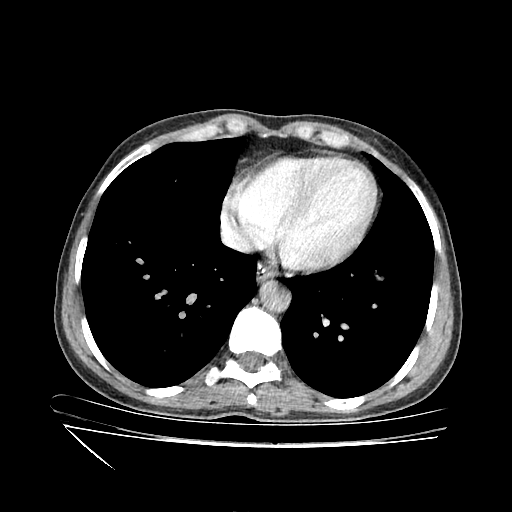

Generated VENOUS CT scan (A→B translation)

Full window (WL 1023.5, WW 4095 β†’ Low βˆ’1024, High +3071)

Actual HU range: [-1024.0, 885.5]

Mediastinum window (WL 40, WW 400 β†’ Low βˆ’160, High +240)

Actual HU range: [-160.0, 240.0]